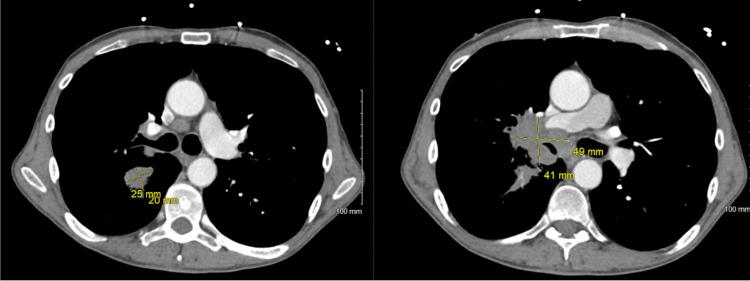

左半结肠切除术的术前实验室检查发现低钠血症,进而发现肺部肿块。

Pre-operative Labs for Left Hemicolectomy Reveals Hyponatremia That Leads to Lung Mass Finding.

副肿瘤综合征是一组具有特定体征和症状的临床病症,与潜在的恶性肿瘤相关。副肿瘤综合征的病理生理学是由各种激素的异位产生或自身抗体的免疫产生引起的。肺癌也因伴有副肿瘤综合征而声名狼藉。与肺癌最常相关的内分泌副肿瘤综合征包括恶性肿瘤高钙血症和抗利尿激素分泌不当综合征(SIADH)。通常,肺癌早期的最初发现之一不是原发性肺癌的症状,而是副肿瘤综合征的症状和/或实验室检查结果。本文旨在介绍一个病例,即一名无症状的肺部肿块患者,其实验室检查值提示SIADH,如何能从低渗性低钠血症检查现状的改变中获益。撰写本文的主要原因是建议将美国预防服务工作组(USPSTF)的一项指南纳入当前低渗性低钠血症的检查中。目前,低渗性低钠血症的检查建议“考虑胸部影像学检查”。然而,将USPSTF的一项筛查纳入医疗服务提供者的问卷中,可能有助于在有吸烟史的患者中更早地发现肺部异常,并且在确定患者是否应接受胸部影像学检查方面也更合适。